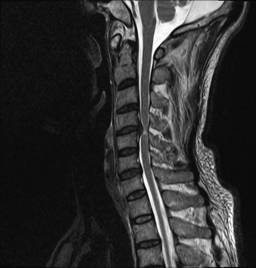

典型病例汇报1:中年男性41岁,因“行走不便2年,加重伴双手麻木2周”之主诉入院,症状主要为:颈部疼痛、僵硬,双下肢无力、行走不稳,双手麻木,协调性差,右手握笔困难。入院查体:步态不稳,C3-C7压痛、叩击痛,肢痛温觉减退,双上肢肢肌力5-级,双下肢肌力4-级,肌张力增高,双下肢腱反射亢进,病理征(+),行颈前路小切口突出椎间盘切除、前路颈椎桥形锁定植骨融合(ROI-C假体),无需前路钢板,术后四肢麻木明显缓解,右上肢精细动作明确增强,可写字,行走不稳消失,肌力基本正常,颈部活动度无明显受限。(1、图2)

图2 术后颈椎X线提示颈椎桥形锁定融合居中,椎间隙高度恢复正常,融合良好